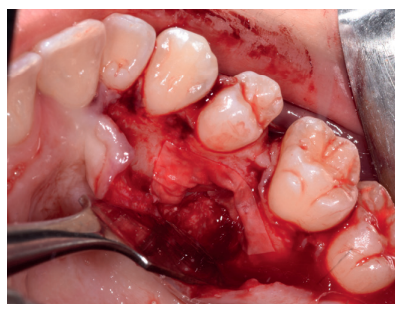

Una vez suturada la herida, se procedió a la extracción del premolar retenido en posición 2.5, para lo cual, tras el bloqueo anestésico de los nervios alveolares superiores posterior, medio y anterior y del nasopalatino y palatino mayor, se realizó una incisión festoneada lineal en la mucosa palatina, y un despegamiento mucoperióstico desde distal del primer molar superior izquierdo hasta distal del incisivo lateral superior izquierdo (Figura 9). Tras el despegamiento, se realizaron las maniobras de ostectomía con pieza de mano y fresa de carburo de tungsteno, la odontosección coronal, y la exodoncia del fragmento coronal y radicular (Figura 10). Al observar la cavidad resultante (Figura 11), se apreció una perforación en la membrana del seno maxilar (Figura 12), en la que se colocó una membrana reabsorbible de colágeno (XFina, Osteógenos®, Madrid, España), de manera previa a la colocación del injerto de dentina (Figura 13). Se le hizo morder al paciente una gasa estéril empapada en clorhexidina al 0,12%, durante la preparación del material de injerto.

Los fragmentos coronal y radicular procedentes del tercer molar inferior y del premolar superior se limpiaron de restos de tejidos blandos y, secos, se introdujeron en la máquina Smart Dentin Grinder® (Kometa Bio, BIONER, España), tal y como aparece en la Figura 14. Tras un ciclo de triturado de 3 segundos, y otro de tamizado de 20 segundos, el material obtenido se limpió con la primera solución durante 12 minutos, y después durante 3 minutos con la segunda solución (Figura 15), para después transportar el material de injerto al alveolo, con presión controlada (Figura 16). Una vez compactado, se colocó una membrana de colágeno (Figura 17) y se suturó la herida con seda de 4/0, mediante puntos periodontales en las papilas (Figura 18). Se realizó una radiografía panorámica en el postoperatorio inmediato (Figura 19).